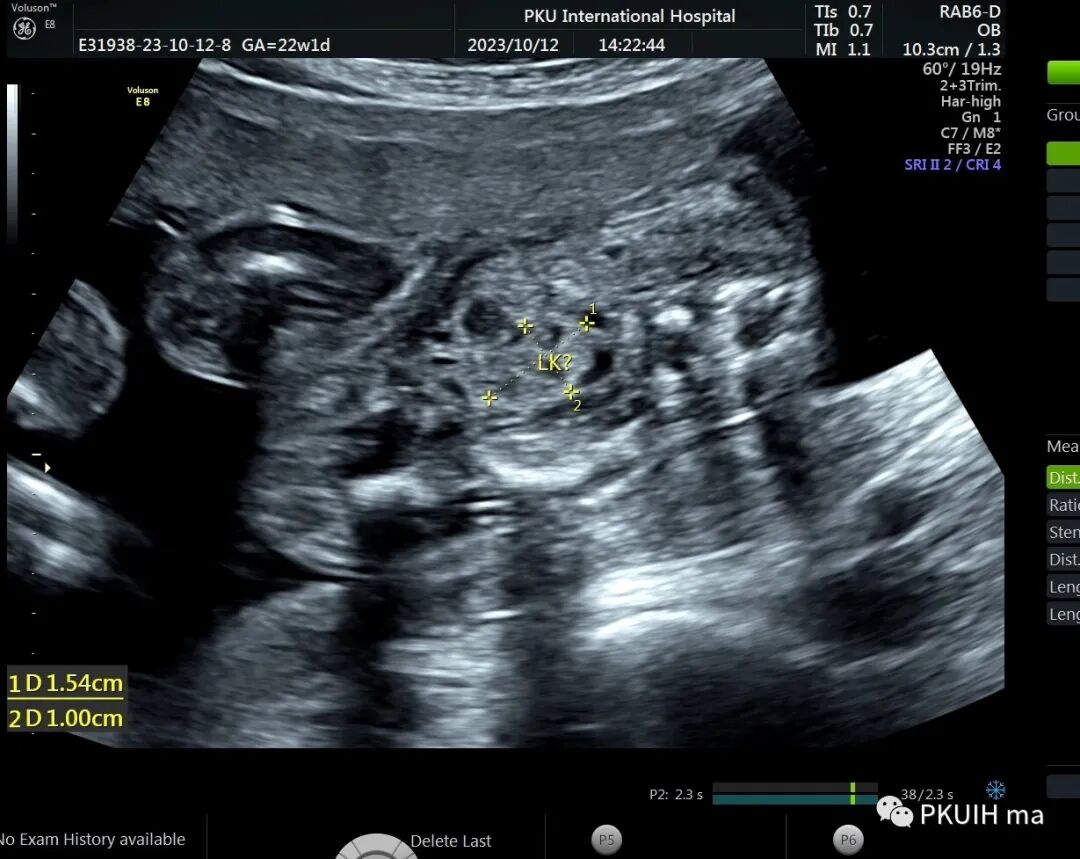

今天看到一22周的胎儿,一侧肾区未见肾脏结构,肾上腺呈平卧征,肾动脉也未显示,在盆腔见到一个发育不良的肾脏回声。

右肾大小位置正常,右肾动脉可见,左肾动脉缺如,正常的左肾区未见肾组织回声,可见肾上腺平卧。于膀胱后上方见一肾组织回声,大小约1.5x1.4x1.0cm,皮髓质分界欠清晰,血供来源于髂动脉。